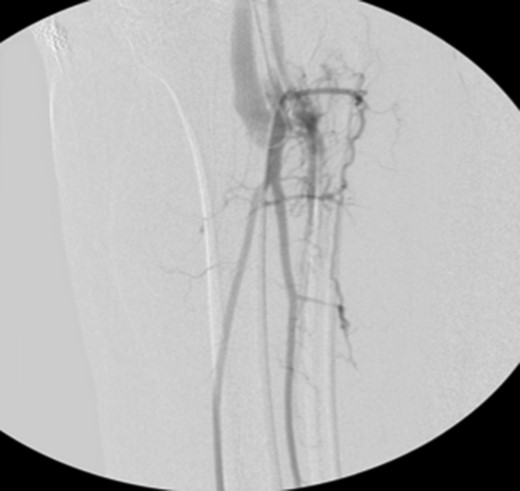

Patient underwent a left lower extremity angiogram. During the procedure she was found to have patent aorta and bilateral common iliac artery. There was no disease visualized in the left external iliac artery, common femoral artery (CFA), SFA, patent previously placed stent, patent above and below the knee PA and two vessel run off to the foot (Fig. 1). Upon delayed fluoroscopic images we identified contrast filling the deep venous system rather quickly suggesting a high volume fistula (Fig. 2). We then identified the fistula between ATA and ATV. Although ATA was previously ligated there was retrograde filling of the artery from unnamed branches, which communicated with the venous system as shown in. In the midcalf (ATA) was cannulated with a micropuncture needle. Micropuncture wire was inserted and a 5-Fr sheath was inserted after exchanging over wire. At this point VortX coils (Boston Scientific) were placed from the curve of ATA until the whole AVF was sealed. Anterograde angiogram showed no flow through the fistula (Figs 3 and 4). There was a palpable PT and DP pulse at the completion of the procedure. Sheath was removed, pressure dressing applied. Patient was discharged home same day. Recovery has been unremarkable. Three months follow-up claudication symptoms have significantly improved.

Fluoroscopy showing; left external iliac artery (EIA), common femoral artery (CFA), superficial femoral artery (SFA), patent previously placed stent, patent above and below the knee popliteal artery (PA) and two vessel run off to the foot.